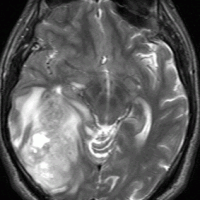

左から、T2強調画像,MRIのFLAIRフレア像,ガドリニウム増強像です。

- フレアとT2で白くぼーっとみえるところは腫瘍のある場所です。腫瘍周辺の脳浮腫も白く映ることがあります。グレード4の膠芽腫では,ガドリニウムという造影剤を使うと右側の写真のように,腫瘍の内部が白く強く増強されます。グレード3ではガドリニウムで増強されないものもあります。びまん性星細胞腫と同様に,実際にはこのMRIで映って見える領域より腫瘍は広い範囲に浸潤して広がっていると考えなければなりません。

- 放射線治療(分割照射)が欠かせない腫瘍ですから,手術後は,病理診断を手早くして放射線治療を計画します。ぐずぐずしていると手術後にまたすぐ腫瘍が大きくなってしまうこともあります。放射線治療にも施設によって技術の差がありますから,その点もしっかり考えます。また後遺症を少なくするためには余分な放射線を当てないということも大切ですが,IMRTなどの放射線治療計画をできるところは多くはありません。

- グレード3と4の星細胞系腫瘍には,手術でできる限り摘出した後に,放射線治療とテモゾロマイド化学療法(制がん剤テモダール)を用いるのが世界の標準治療です。

- 特に,手術で最大限に腫瘍を摘出できたときに治る確率は高くなりますが、脳を腫瘍と一緒に取ることになりますのでひどい後遺症を残すような手術はしません。またどのような手術手段(ナビゲーションや覚醒下手術や術中MRI)を用いても,膠芽腫が完全摘出できるということは絶対にあり得ません。

- 放射線治療は,50-60グレイくらいの線量が必要ですが、腫瘍の広がりと部位によっては腫瘍の増殖は抑制されても知能の低下などの放射線障害が出ることがあります。しかし,放射線治療をしないと長期生存は期待できません。